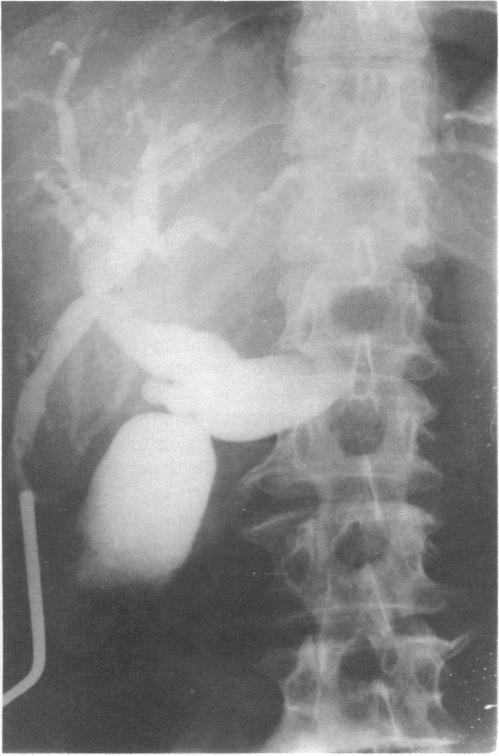

Transcholecystic operative cholangiography: an alternative technique.

Percutaneous transcholecystic cholangiography: experimental study.

Intraoperative cholangiography for laparoscopic cholecystectomy.

CHOLANGIOGRAPHY: VISUALIZATION OF THE GALLBLADDER AND BILE DUCTS DURING AND AFTER OPERATION.

Cystic-duct cannula and cannula-holding clamp for operative cholangiography.